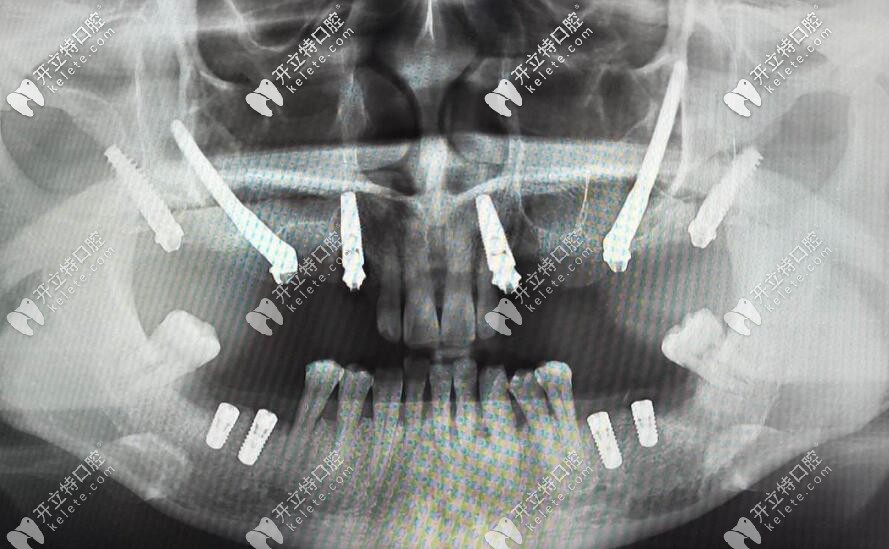

開展項目:全口/半口種植牙、各種疑難種植牙,穿顴穿翼等高難度種植牙技術(shù)。

穿顴穿翼種植牙技術(shù)

從事口腔種植牙臨床已經(jīng)有十多年,種植牙顆數(shù)達上萬顆,而且就診于合肥口腔種植中心,當然合肥美奧口腔還有MCIC復雜病例種植牙中心,專門為缺牙者進行的口腔解方案的制定。